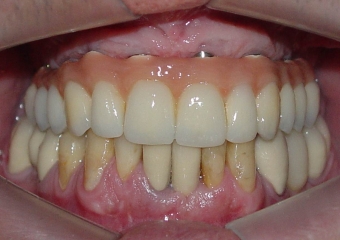

Raio X da prótese fixa em porcelana superior

Prótese fixa em porcelana superior

Sorriso do caso terminado em abril de 2012